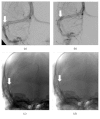

Results: Seventy-nine patients were diagnosed with IIH. Bilateral transverse sinus stenosis (TSS) was found in 74% of the population. Visual outcome at 6 months was poor for 46% of patients, including all patients presenting weight gain of at least 5% since diagnosis (p < 0.001), whereas mean body mass index at diagnosis was not different between patients with poor versus good outcome (32.9 ± 7.7 versus 34.6 ± 9.4 kg·m-2). Other significant factors of poor prognosis were bilateral TSS (OR = 5.2; 95 CI: 1.24-24.9; p = 0.024). Thirteen patients with poor outcome after 6-month assessment underwent unilateral TSS stenting leading to visual improvement in 11 cases.

Conclusion: Weight gain, rather than initial weight, emerged as the leading factor of poor visual outcome in patients with IIH, followed by presence of bilateral TSS. Consequently, first-line treatment must include dietary measures to control weight. Unilateral stenting appears to be a safe second-line treatment option for patients with bilateral TSS.